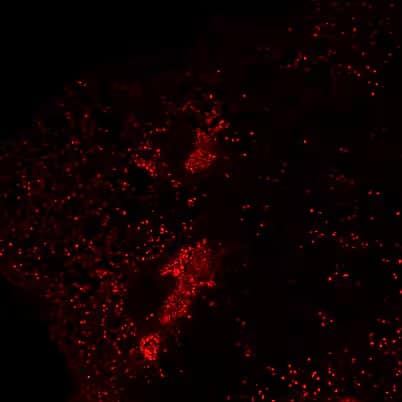

Immunohistochemistry: SARS Nucleocapsid Protein Antibody [NB100-56576] - Immunostaining of severe acute respiratory syndrome coronavirus 2 in pulmonary tissues from fatal coronavirus disease cases. A) P5 (Patient 5): scattered immunostaining of tracheal epithelial cells. B) P5: higher magnification shows immunostaining of ciliated cells. C) P8: immunostaining of desquamated type I pneumocyte in an alveolar lumen. D) P4: colocalization of SARS-CoV-2 viral antigen (red) with type II pneumocyte stained by surfactant (brown; arrow). E) P4: colocalization of SARS-CoV-2 viral antigen (red) with macrophages stained by CD163 (brown; arrows); virus immunostaining within type II pneumocytes is also seen (arrowheads). F) P4: extensive immunostaining of hyaline membranes in a region of exudative DAD. G) P3: scattered immunostaining within macrophage in hilar lymph node; anthracosis is also present. Emerg Infect Dis. 2020 May 21;26(9) 10.3201/eid2609.202095, PMID: 32437316